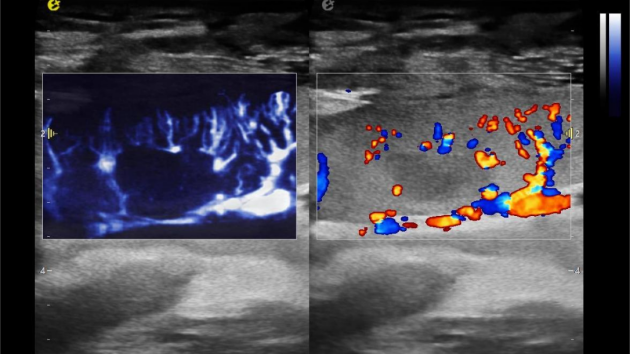

开启肾移植微观视界 | 银河官网黑科技为您“移”路护航(图4)

开启肾移植微观视界 | 银河官网黑科技为您“移”路护航(图5)

在肾移植领域,医生最怕的不是手术刀下的惊心动魄,而是那些手术后肉眼看不见的危机——急性排斥反应导致的血小板聚集形成的微血栓、毛细血管网损伤等...这些“隐形杀手”曾让无数移植肾在悄无声息中衰竭。而银河官网医疗(ESI)的iPlane Vascular平面波超微细血流显像技术,正是为破解这一难题而生。

开启肾移植微观视界 | 银河官网黑科技为您“移”路护航(图6)

超微视血流显像显示肾脏五级血管

开启肾移植微观视界 | 银河官网黑科技为您“移”路护航(图7)

微米级超高分辨率血流信号显像

开启肾移植微观视界 | 银河官网黑科技为您“移”路护航(图8)

肾脏的灌注评估,RI/VI量化数据

开启肾移植微观视界 | 银河官网黑科技为您“移”路护航(图9)

开启肾移植微观视界 | 银河官网黑科技为您“移”路护航(图10)

开启肾移植微观视界 | 银河官网黑科技为您“移”路护航(图11)

超微视血流显像评估肾移植术后灌注情况